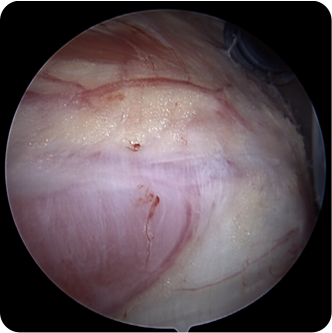

회전근개파열의 여러 모습들

기존의 삼각근을 절개하고 회전근개를 노출시켜서 수술하는 방법이 아닌 초소형 카메라인 관절내시경을 삼각근을 통과시켜 회전근개파열을 봉합합니다. 힘줄 주변의 근육 손상을 최소화시킬수 있기 때문에 수술 후 유착 반응이나 통증 반응이 감소하여 빠른 재활이 가능합니다.